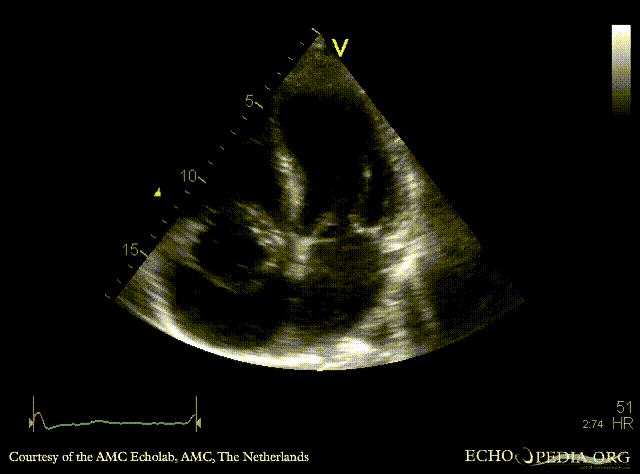

Case 37

Abscess of aortic root

PSAX: abscess of aortic root A4CH: large abscess of aortic root